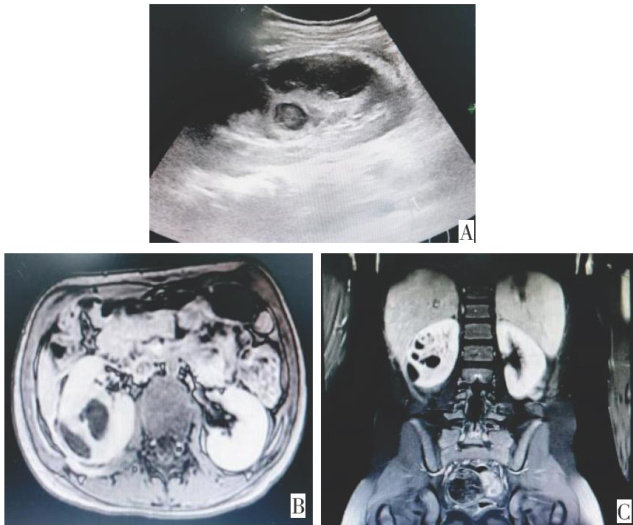

摘要:儿童肾脓肿是一种少见的泌尿系统感染性疾病,其临床表现常不典型,给临床医生的诊断带来巨大的挑战。文章报告了1例肾脓肿患儿,该患儿间断发热,最终确诊肾脓肿,抗感染及穿刺引流后痊愈,完善肾脓液病原微生物宏基因组检测示脆弱拟杆菌,文章从诊断、治疗、实验室检测及预后问题进行探讨。